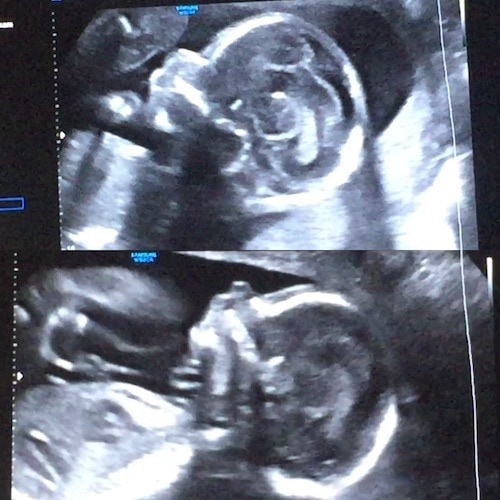

- Ultrasound Photos at 24 Weeks Pregnant With Twins

Ultrasound Photos at 24 Weeks Pregnant With Twins